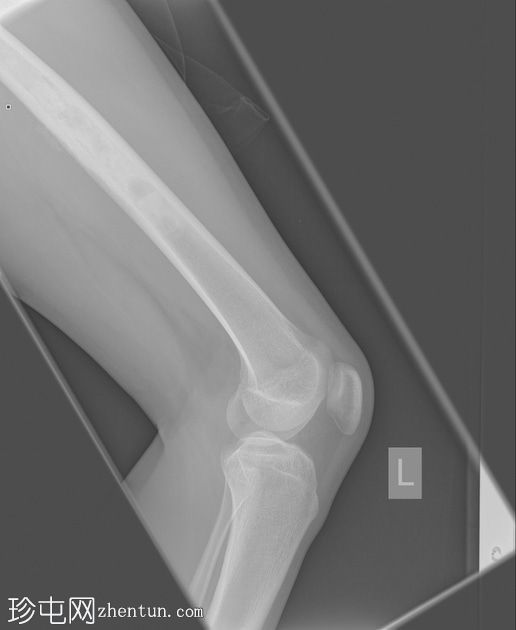

X光片

侧面

左股骨中段可见边界不清的硬化区域,伴有宽阔的过渡区和虫蛀状外观。

邻近软组织可见小块钙化灶。无骨折或脱位。